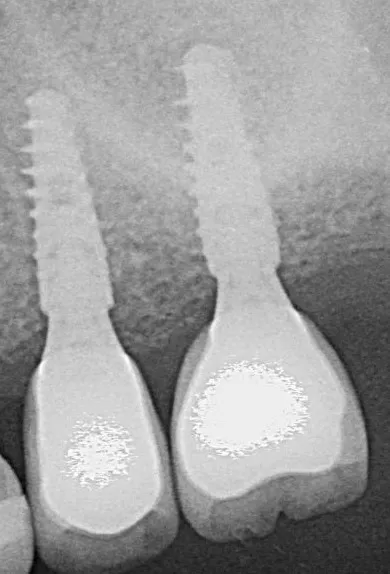

9-10-11. The patient had D3 bone density. Hence an undersized drilling protocol was employed, the final drill diameter being one less than that of the implant. The green drill was used for the 25 implant (diameter 3.4) and the red one for the 26 (diameter 4.0).

12a-b-c. The design of the Axiom X3® ensures atraumatic implant placement with the micro motor. The Axiom X3® also preserves bone, even if the ridge is thin and resorbed. Despite the meager quantity of vestibular cortical bone, there was no perforation or rupture of the crestal margin.

13. The implants were placed 0.5–1 mm subcrestally. Note the thinness of the vestibular cortical bone at the 25 implant on this occlusal view. Despite this, we achieved perfectly acceptable stability values of 19 and 20 Ncm.